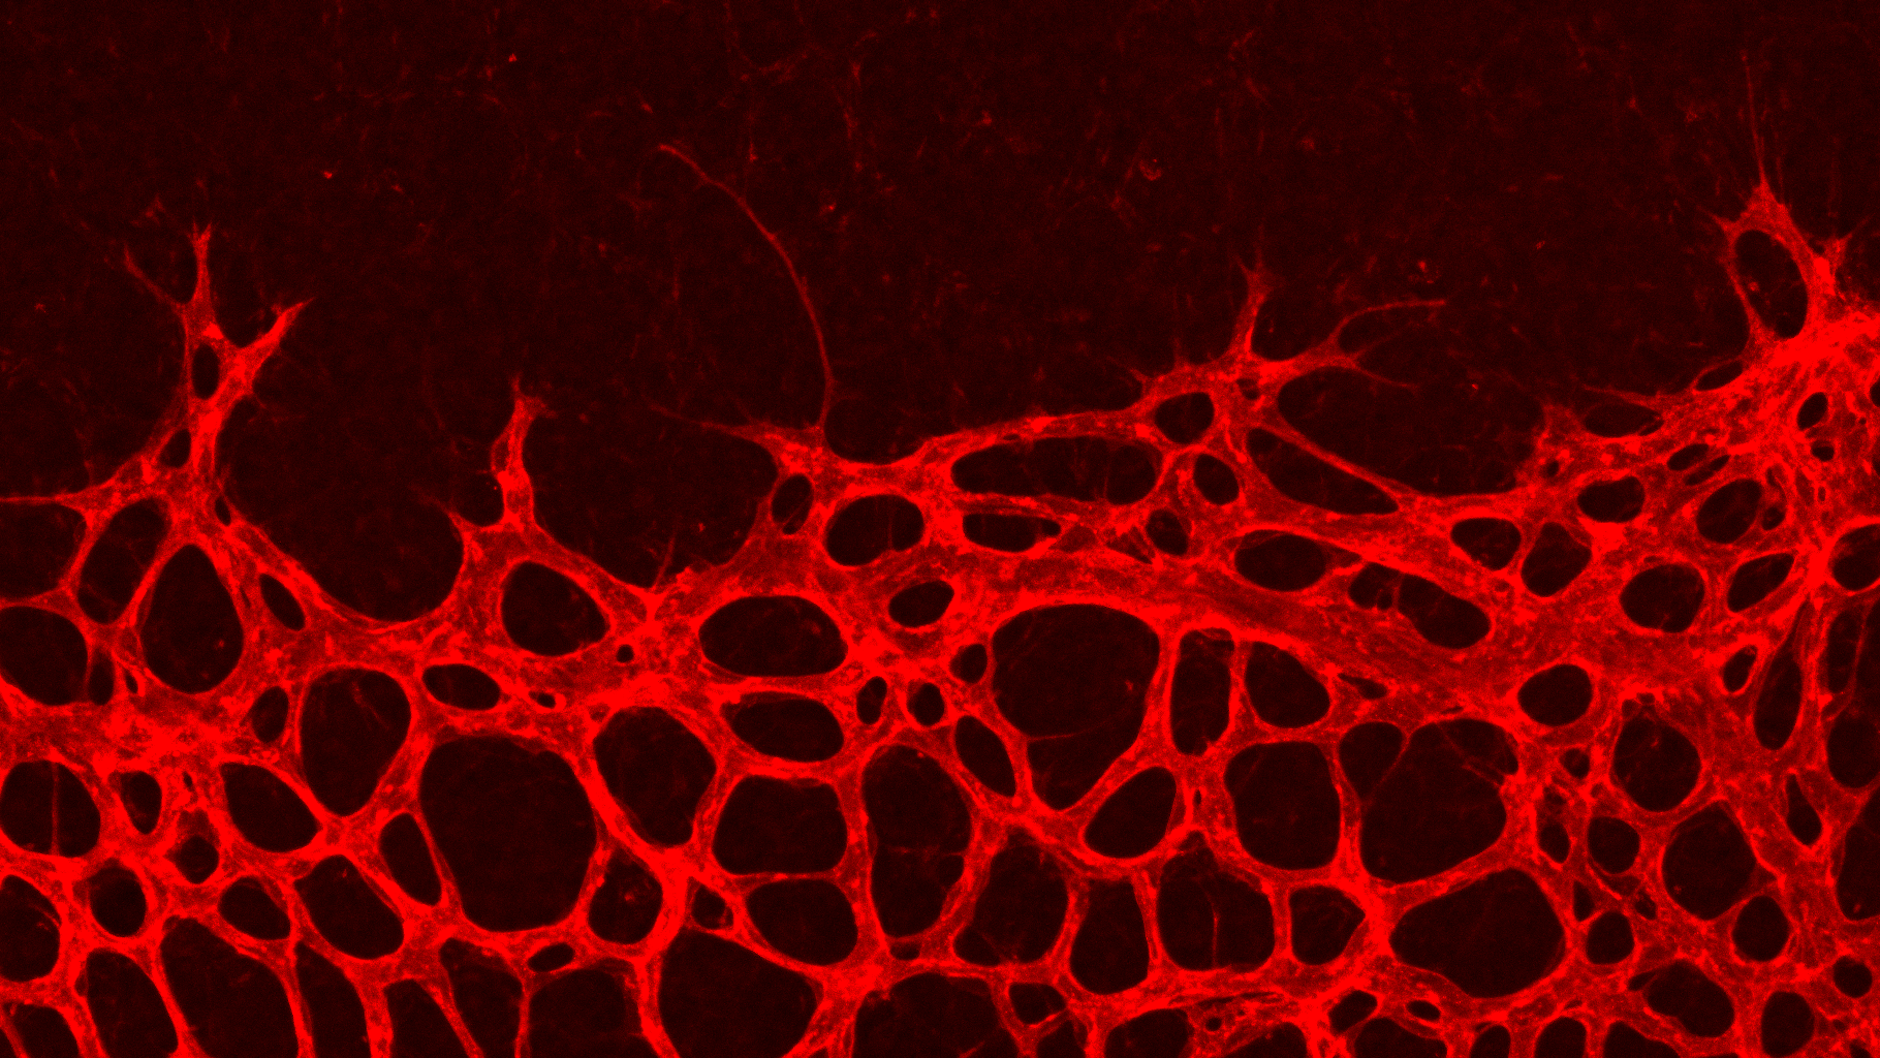

Sie entdeckten vor etwa zwei Jahrzehnten die sogenannte Aussprossung der Blutgefäße. Bildlich gesehen handelt es sich um lange, fadenförmige Auswüchse von Leitzellen, die nachfolgenden Zellen die Richtung weisen. Daraus bauen sich feine Kapillaren auf, die sich zu einem Netz verbinden. Sind solche Vorgänge wichtig, um Krankheiten zu verstehen, die mit den Blutgefäßen zusammenhängen?

Ja, der Grundansatz ist, dass wir erst einmal verstehen wollen, wie die einzelnen Zellen zusammenarbeiten, um das geordnete Muster zu bilden. Verantwortlich für die neue Aussprossung von Blutgefäßen sind die sogenannten Endothelzellen, die die innere Auskleidung aller Gefäße bilden. Sie weisen den neuen Gefäßen den Weg. Erst dann werden die unterstützenden Glattmuskelzellen rekrutiert, um die Gefäße zu verstärken. Endothelzellen sind so wichtig, weil sie ähnlich wie Nervenzellen sehr langlebig sind. Was wir an Schädigungen über Jahrzehnte dort mitnehmen, das bleibt auch. Und das bestimmt vermutlich auch, wie zukünftige Krankheitsverläufe ablaufen.